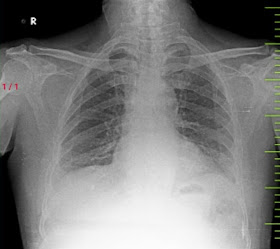

Chest Xray

ECG